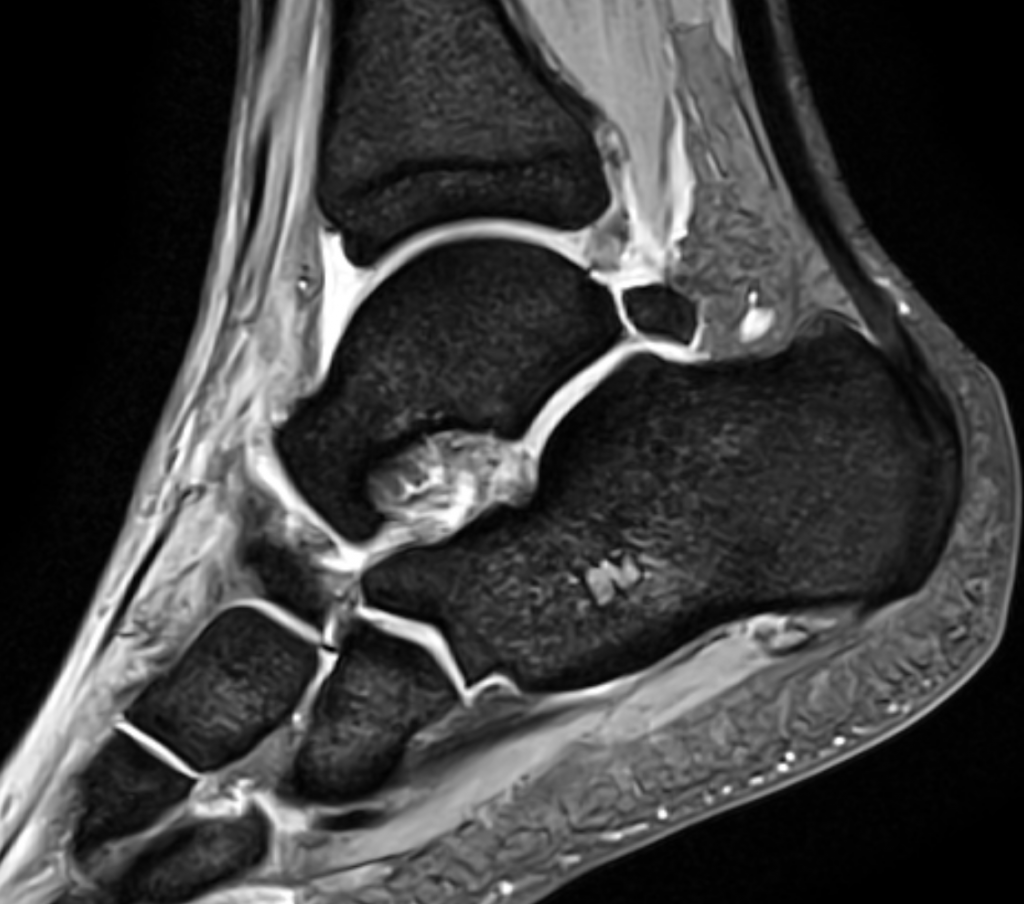

From faoj.org

Subtalar dislocation The Foot and Ankle Online Journal Eds Ankle Issues ankle and foot hypermobility is a common symptom, affecting a significant portion of adults with eds. — ankle instability is a common problem with eds patients. Both dislocations and subluxations can be. procedures around the ankle have a high failure rate, and wound problems are common. These problems often resolve spontaneously or with physical therapy or other. Eds Ankle Issues.